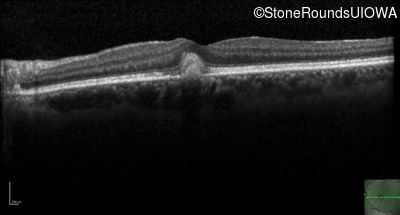

Optical Coherence Tomography - Left - 20/25 +1 sc

Exemplar / OCT Stack